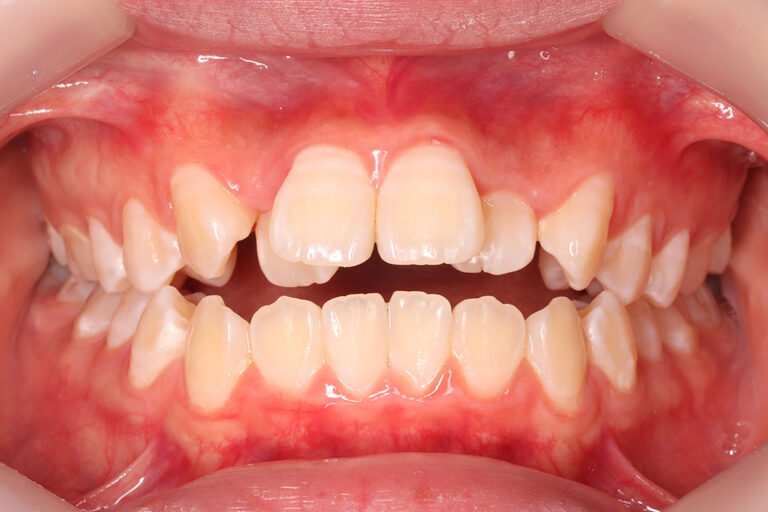

上顎前歯の強い叢生(がたつき)と、前歯部開咬状態でした。

治そうという意識が強い方でしたので、顎間ゴムの協力も良かったです。

治療期間が平均よりやや短く2年2か月でした。

治療前、開咬で舌癖の強い方は一般的に後戻りしやすいのですが、

装置撤去後1年10か月経過していますが安定しています。

マルチブラケット 動的治療期間 2年2か月 調整回数22回